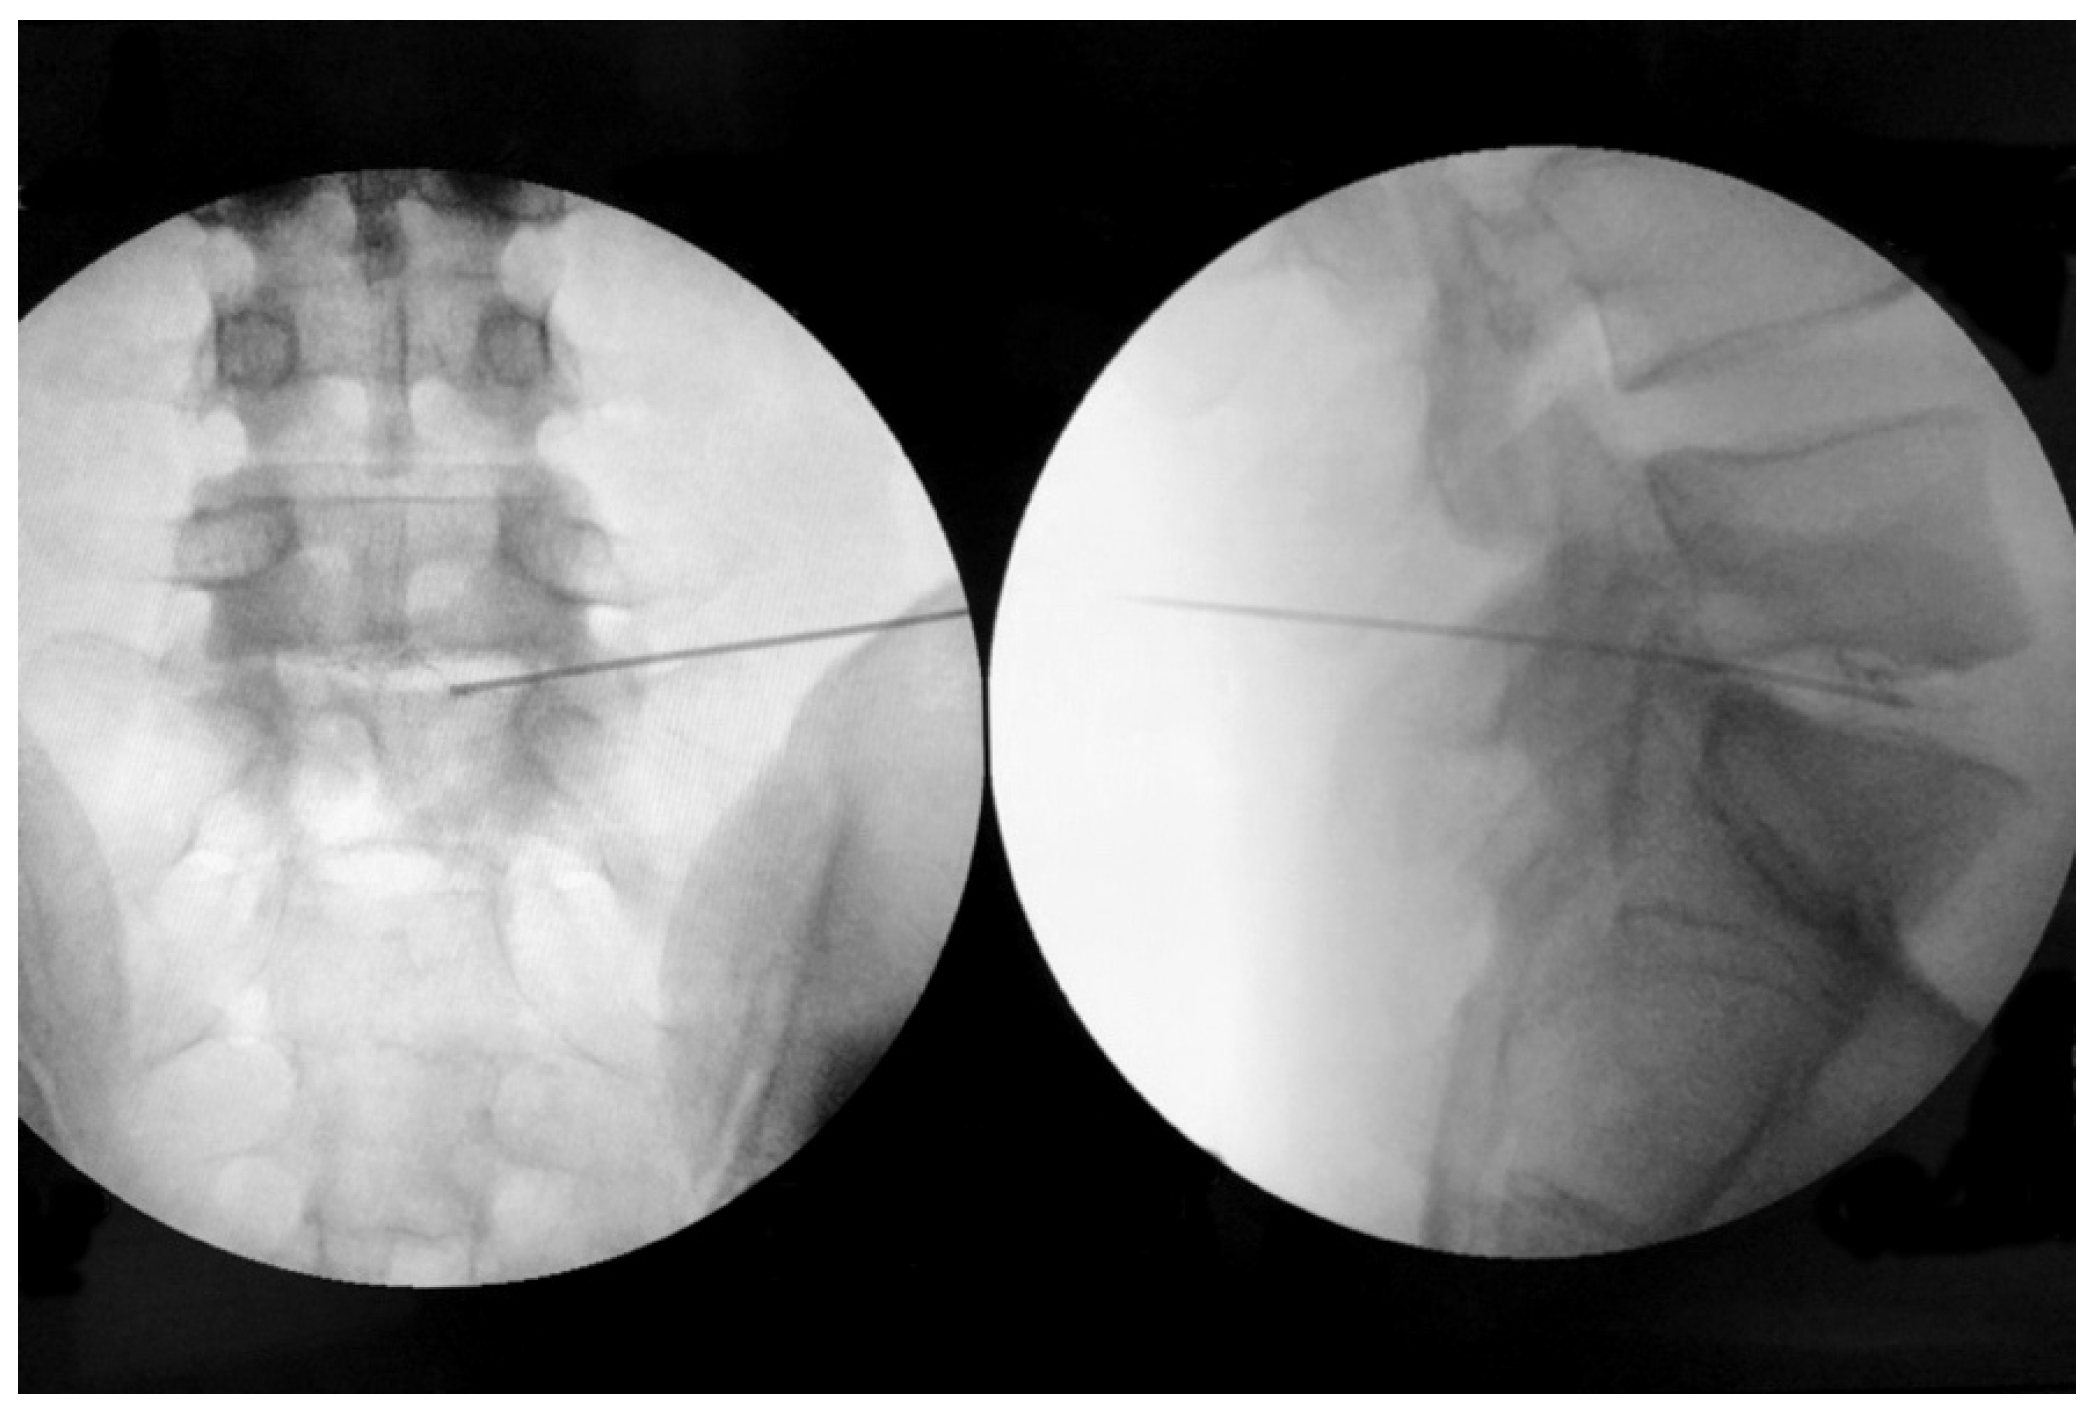

2.2. Procedure